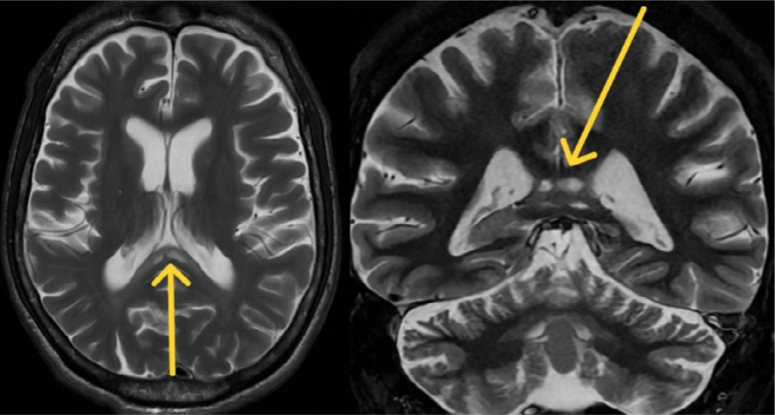

Co-occurrence of radiological signs of Marchiafava-Bignami disease and alcohol-related cerebellar degeneration.

Marchiafava-Bignami病和酒精相关性小脑变性的影像学征象共同出现。